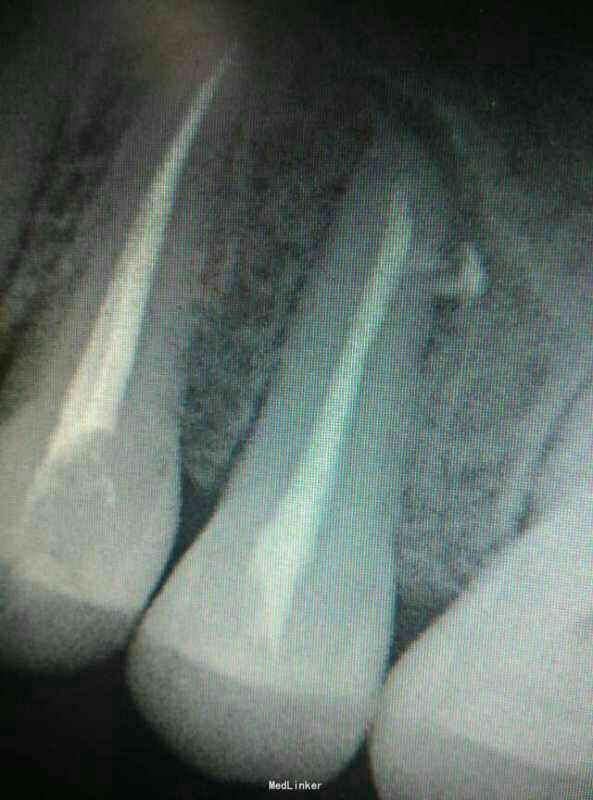

想兼职被要求发病例当代表作,手机里只有今年一月份随手拍下来的当月的几张病例X光片,发出来权当代表作,欢迎大家批评指正。主要是拔牙和根管治疗。

后牙根管再治疗